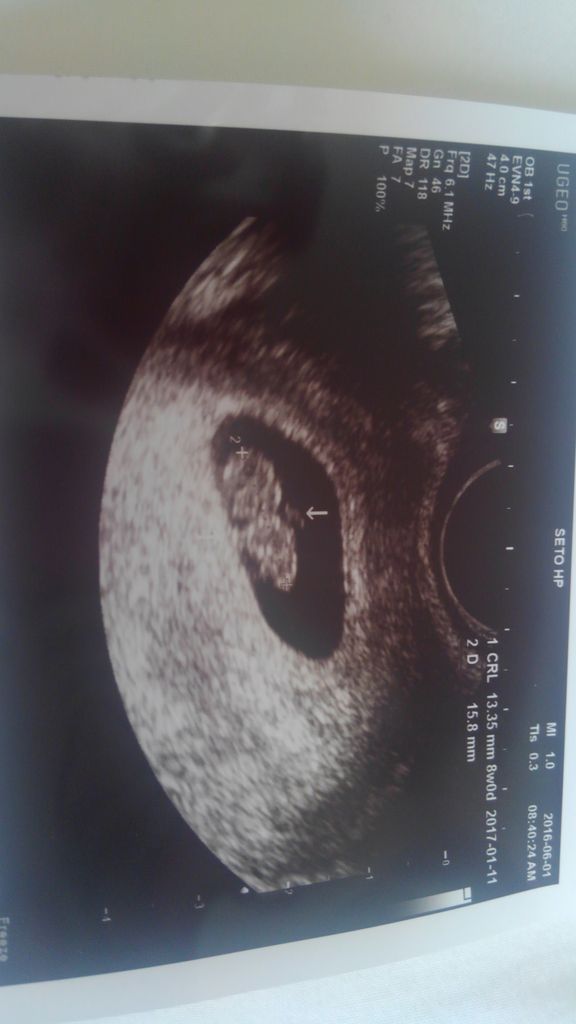

医師監修 妊娠7週のエコー写真を多数掲載 みんなのエピソードつき 年9月17日 ウーマンエキサイト 2 3